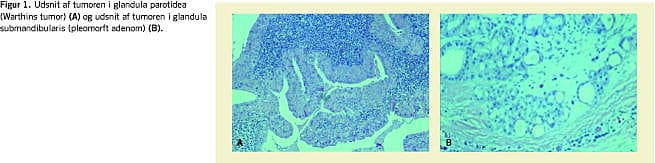

Histologien bekræftede FNA-diagnosen (Figur 1 ). I gl. parotidea fandt man mikroskopisk en tumor, der havde adenopapillære og cystiske strukturer og var beklædt med toradet onkocytært epitel. Subepitelialt blev der fundet lymfoidt væv med kimcentre. Der var ingen tegn på malignitet. I gl. submandibularis var der en tumor, som overalt var velafgrænset mod det omgivende spytkirtelvæv. Selve tumoren havde vekslende udseende med ligeligt fordelt stromal og epitelial komponent og dukter. Der fandtes ingen tegn på malignitet. Der var således tale om WT i gl. parotidea og PA i gl. submandibularis.